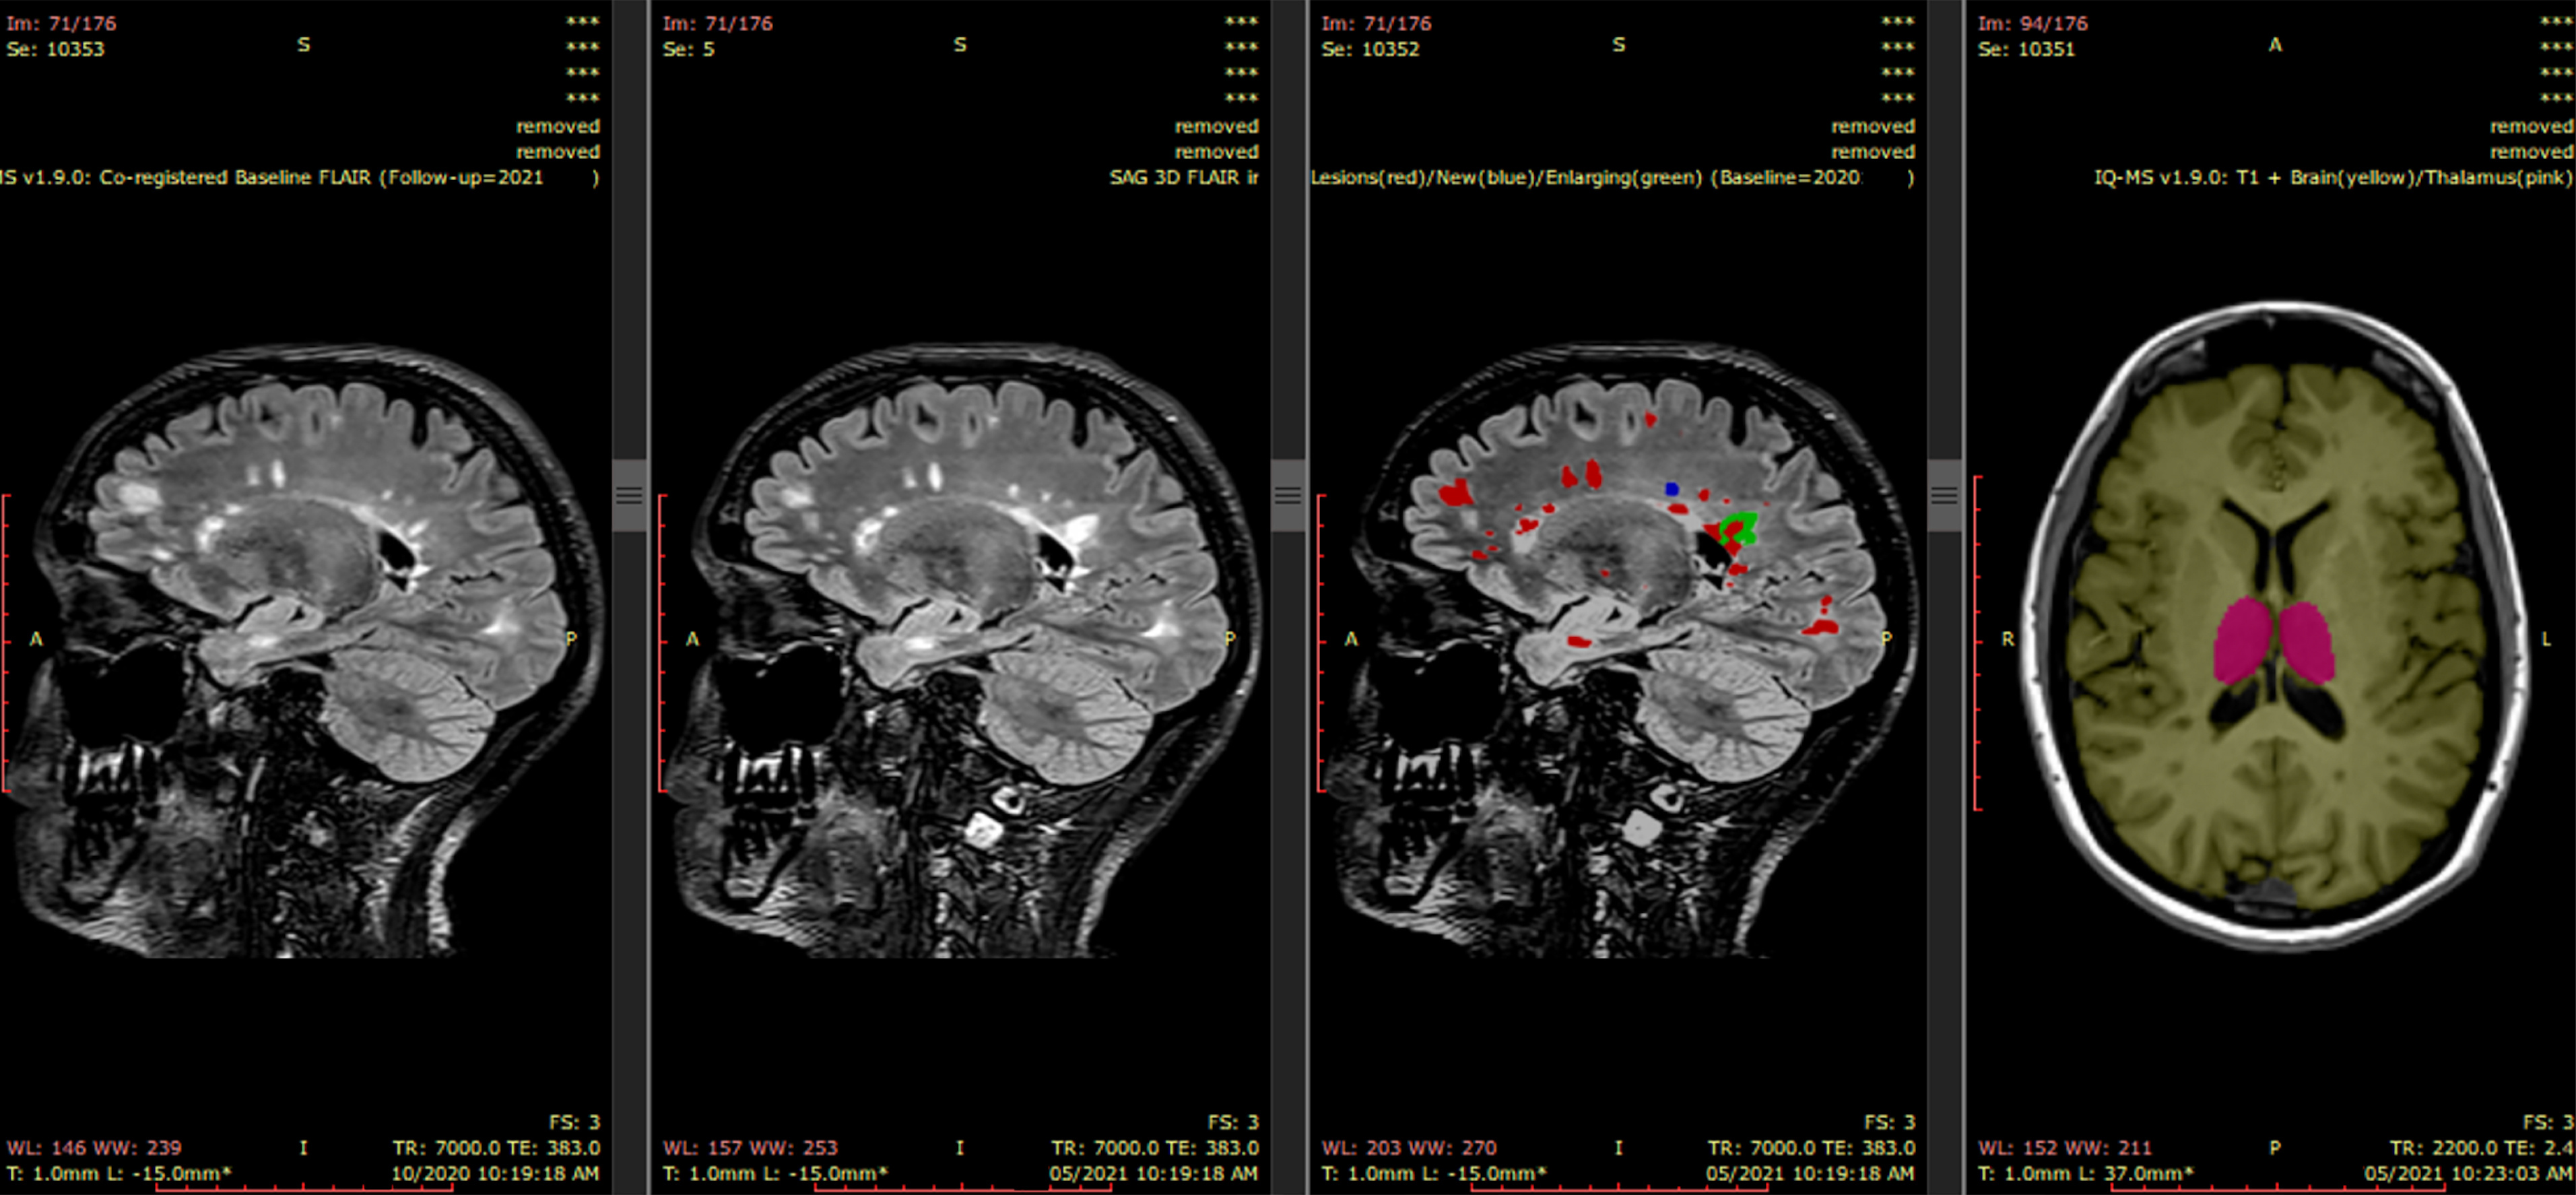

Figure 1. iQ-Solutions PACS visualization

iQ-SolutionsTM automatically returns a co-registered baseline (prior study) 3D FLAIR series together with a lesion-annotated 3D FLAIR, here showing a case with both new (blue) and enlarging (green) lesions.  A 3D-T1 series is also returned with both whole brain (yellow) and thalamus (pink) annotations.